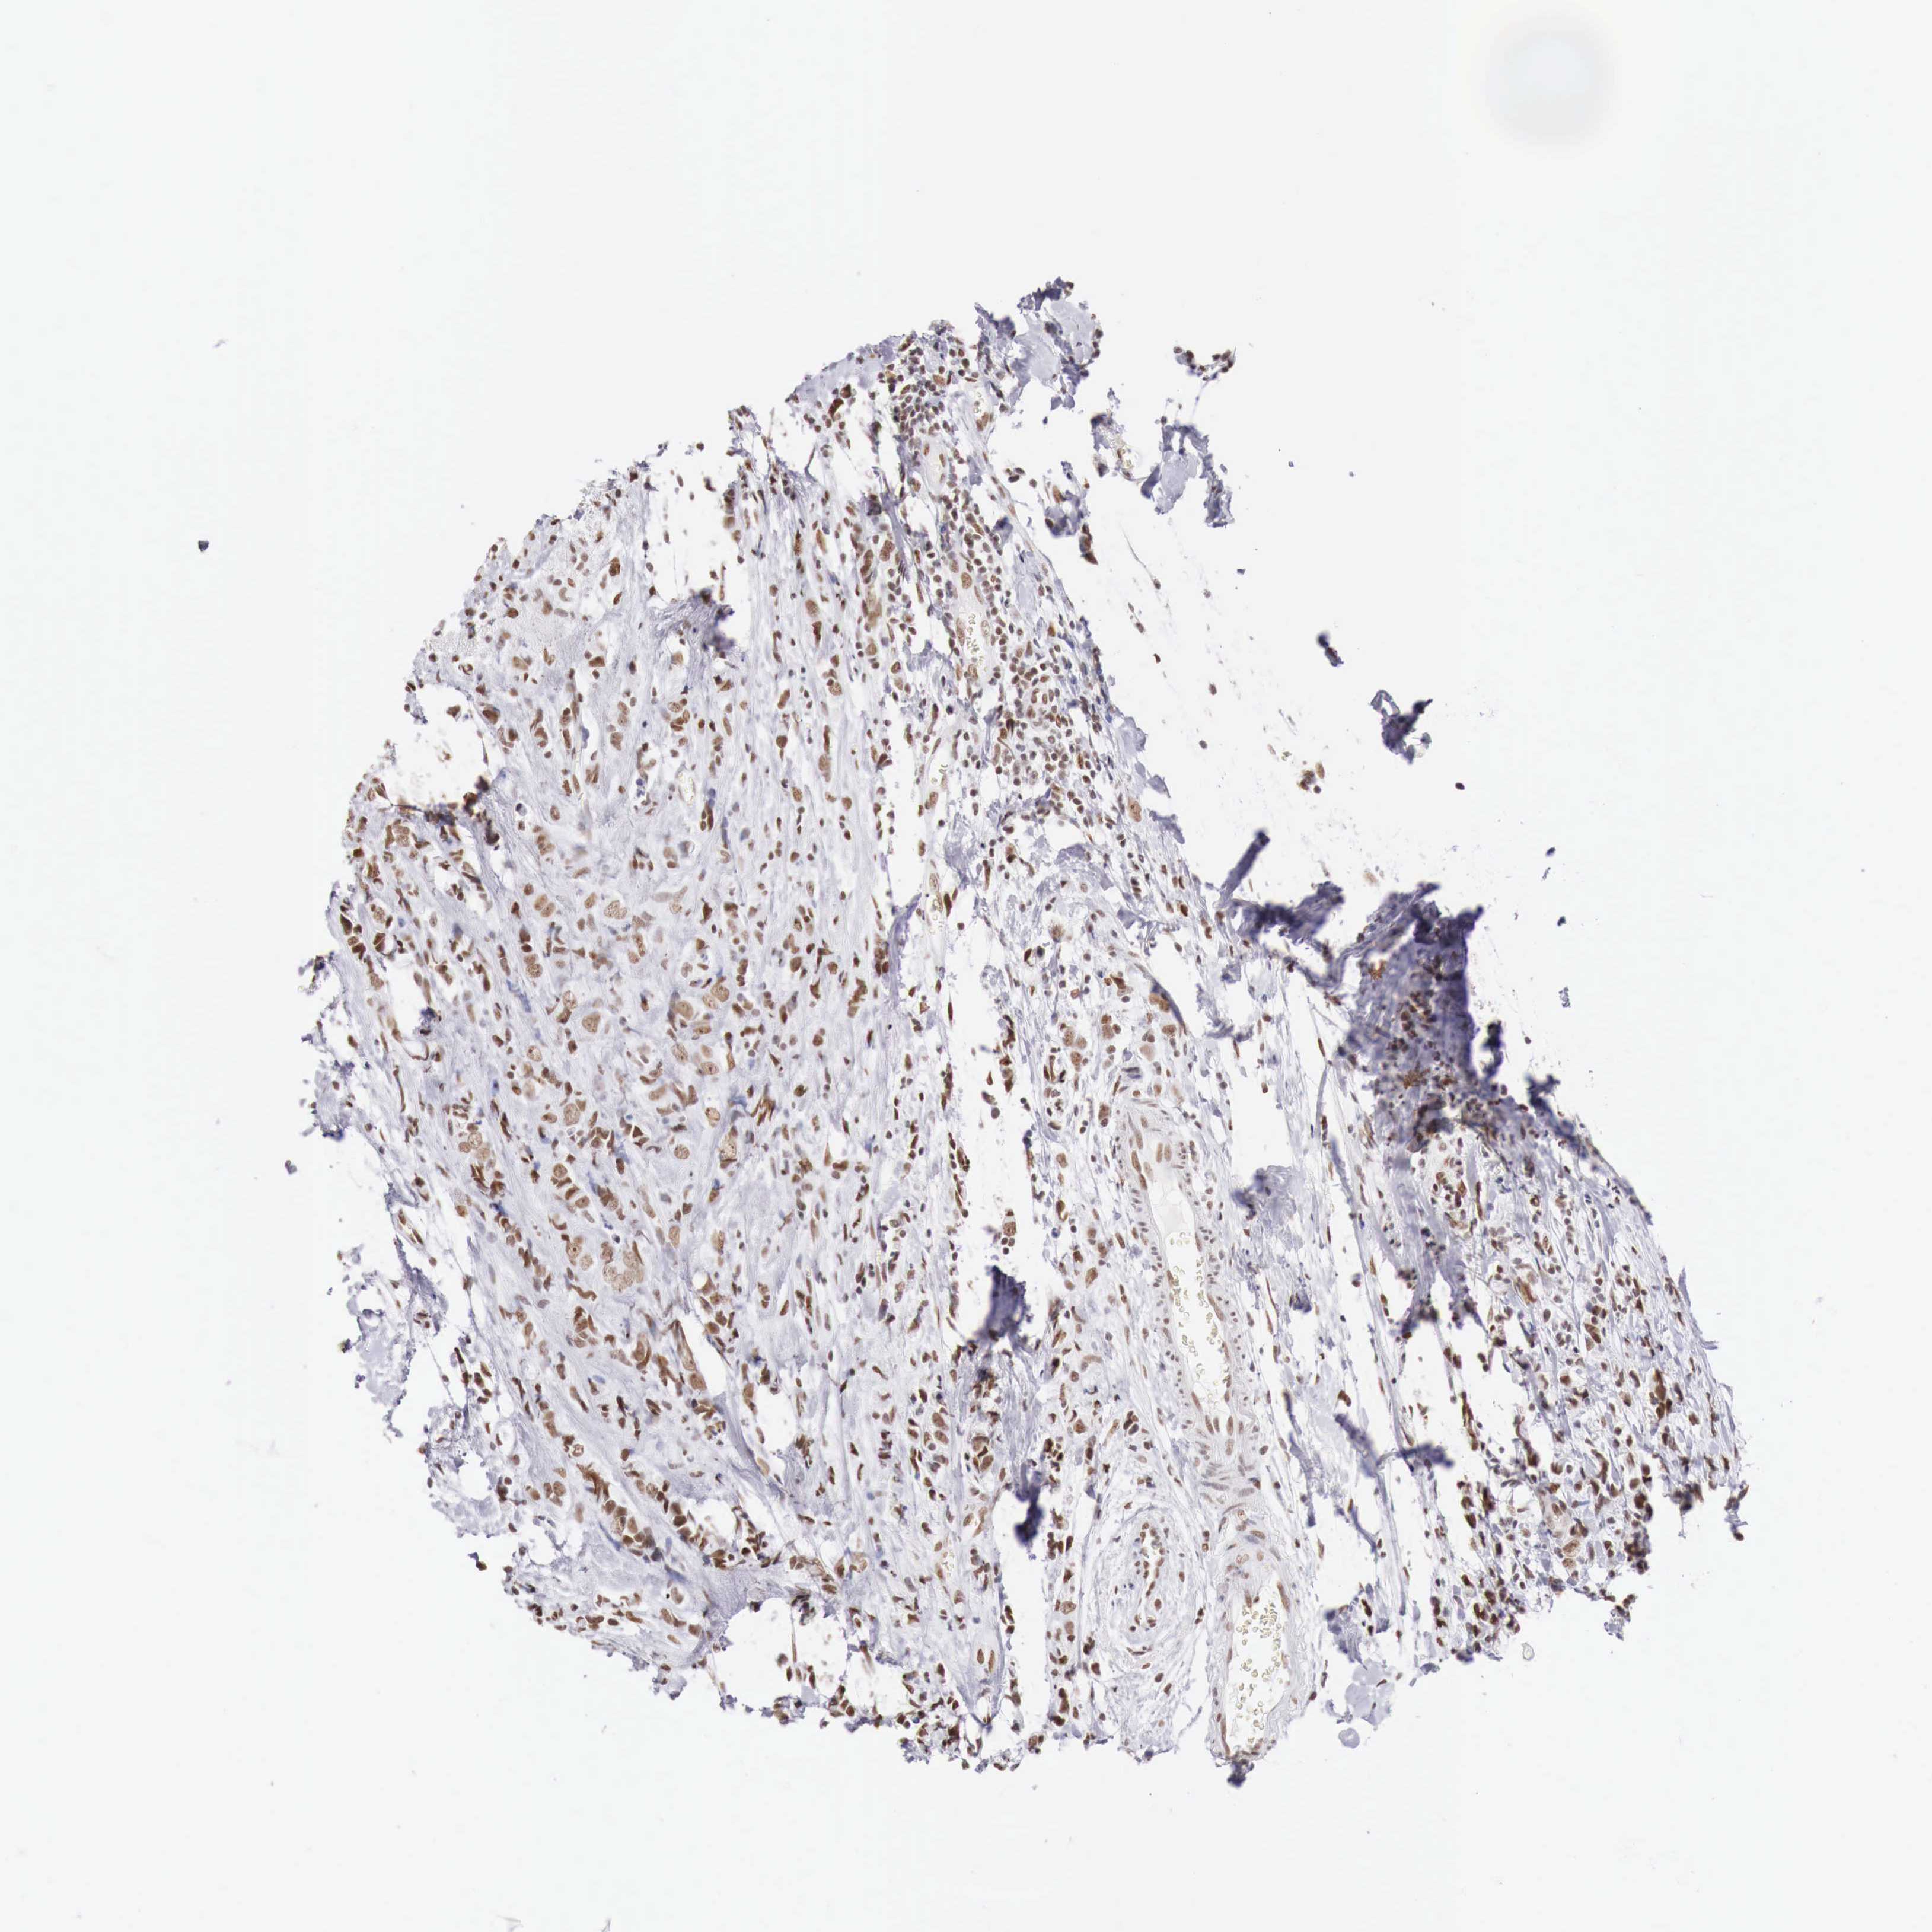

CANCER BREAST CANCER Show tissue menu

Breast cancer

Human cancer